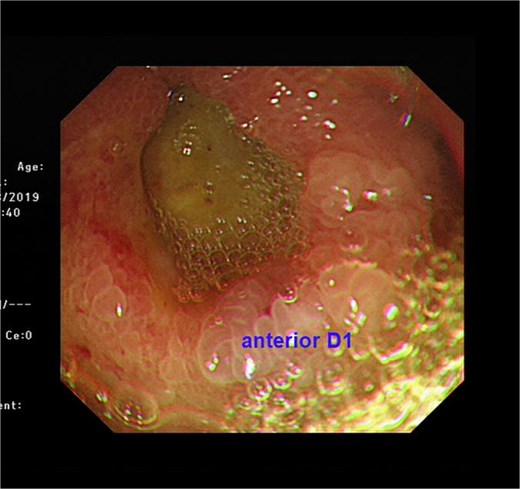

A 74-year-old man who had history of hypertension and diabetes mellitus presented with upper gastrointestinal bleeding. Upper endoscopy revealed deformed pylorus and a 1 cm deep ulcer at anterior wall of first part of duodenum (Fig. 1). Computed tomography (CT) revealed a 4.8 cm exophytic hypoenhancing mass at segment 4a of liver with dilated left intrahepatic duct (Fig. 2). There was aerobilia suggestive of choledochoduodenal fistula. There was also suspicion of diaphragm invasion. Serum carcinoembryonic antigen (CEA) was elevated to 83ug/L while alpha-fetoprotein (AFP) was normal. Both the hepatitis B surface antigen and anti-hepatitis C antibody were negative. Positron emission tomography (PET) confirmed a hypermetabolic liver tumor but no distant metastasis. The clinical diagnosis was ICC with suspected duodenal and diaphragmatic invasion. The patient was offered radical resection for tumor.

CT showing showing an exophytic hypoenhancing mass at left liver with dilated left intrahepatic duct.